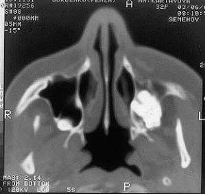

Рисунок 6 – Схема спирального сканирования 2.3 Получение компьютерной томограммы Получение компьютерной томограммы (среза) на выбранном уровне основывается на выполнении следующих операций: 1) формирование требуемой ширины рентгеновского луча (коллимирование); 2) сканирование пучком рентгеновского излучения, осуществляемого движением (вращательным и поступательным) вокруг неподвижного объекта устройства «излучатель – детекторы»; 3) измерение излучения и определение его ослабления с последующим преобразованием результатов в цифровую форму; 4) машинный (компьютерный) синтез томограммы по совокупности данных измерения, относящихся к выбранному слою; 5) построение изображения исследуемого слоя на экране видеомонитора (дисплея). Пример рентгеновской компьютерной томограммы на рис. 9.

Рисунок 7 – Компьютерная томография верхнечелюстных пазух. Сверхкомплектный зуб в левой гайморовой пазухе. Строго коллимированный пучок рентгеновского излучения проходит только через ту плоскость, которая интересует врача (рис. 10). При этом регистрация рассеянного излучения сведена к минимуму, что значительно улучшает визуализацию тканей, особенно мало контрастных. Снижение регистрации рассеянного излучения при компьютерной томографии осуществляется коллиматорами, один из которых расположен на выходе рентгеновского пучка из трубки, другой – перед сборкой детекторов.